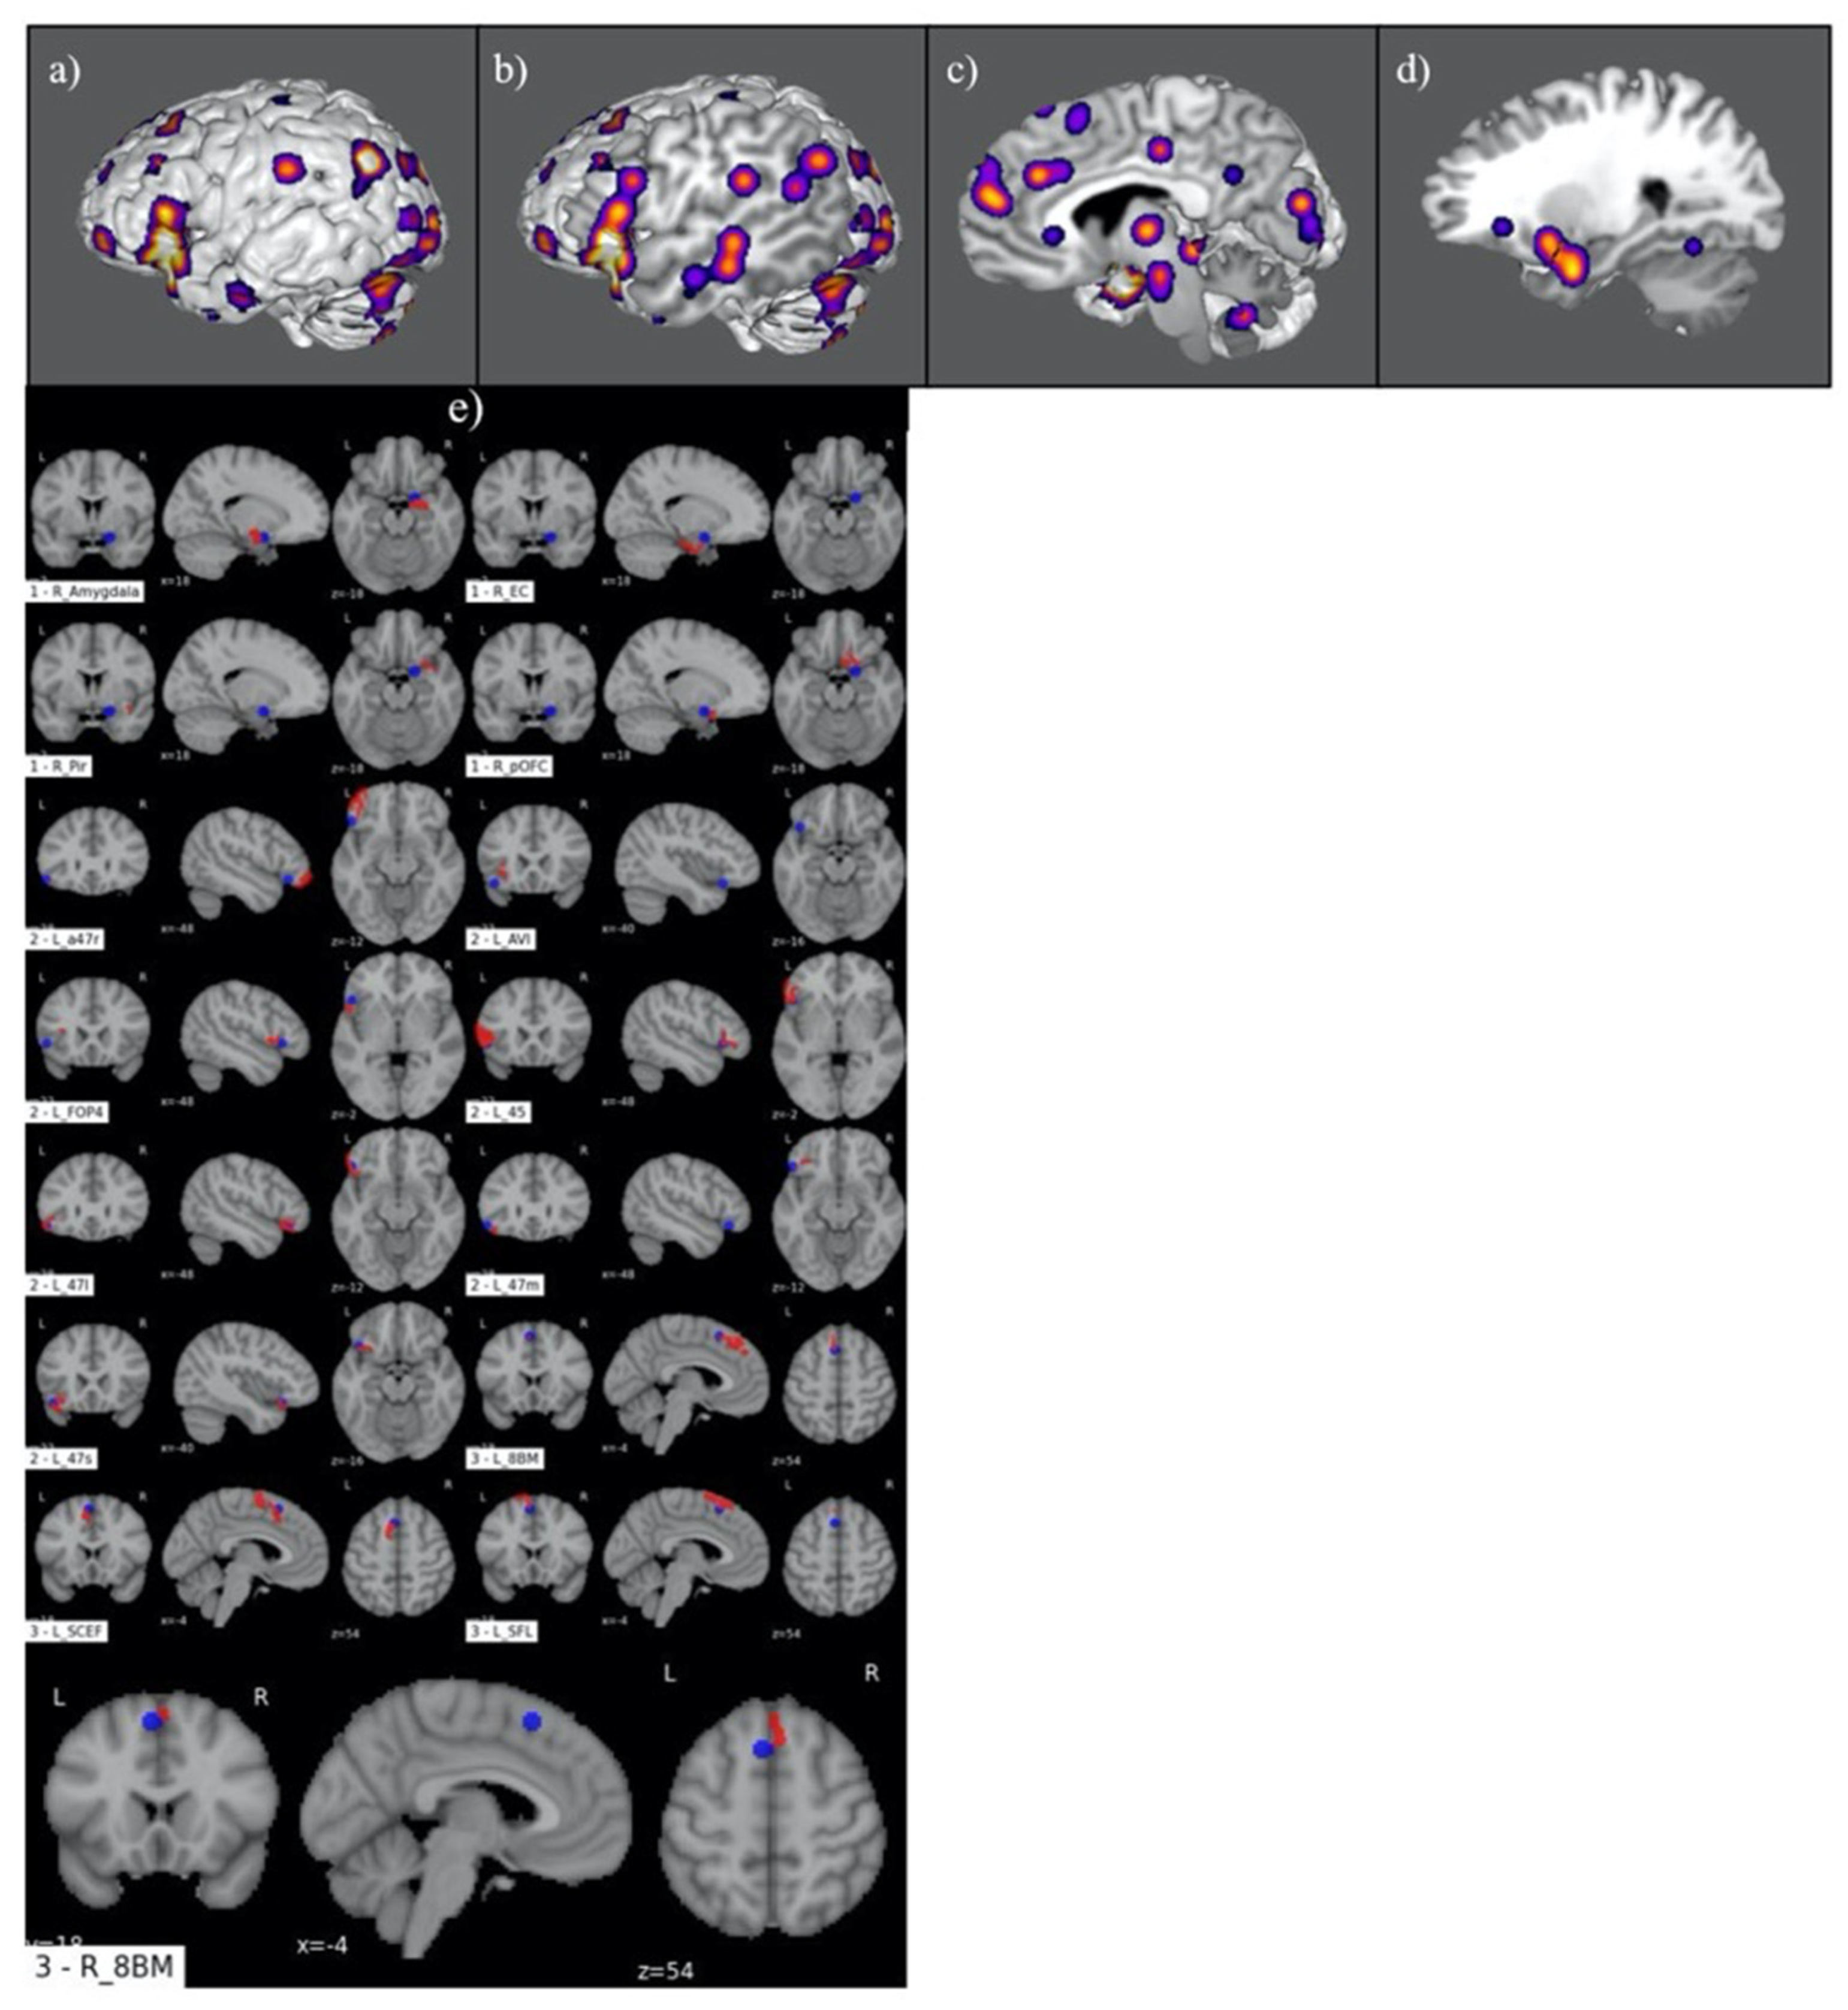

3.1. Judgement Activation Maps

3.2. Parcellation-Based Comparative Analysis